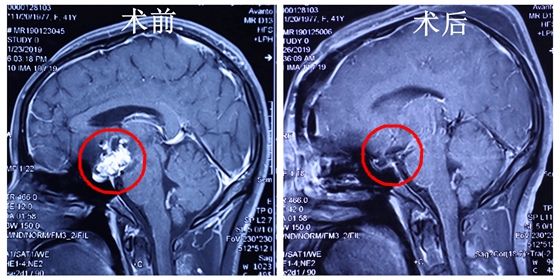

2019年1月24日,袁贤瑞教授开始为余女士手术。病变位于鞍上-三脑室底部,并向左侧鞍旁、颈内动脉外侧及斜坡方向生长,左侧动眼神经、颈内动脉、视神经、左侧大脑前动脉与肿瘤粘连紧密,并被包绕。眼前的凶险果然如袁教授所想的那样。经过艰苦7小时手术,袁贤瑞教授在以毫米计算的手术空间内顺利完成颅咽管瘤全切术,切除了大小约4*3*3厘米的肿瘤,术中出血仅300毫升,患者术后平稳,十天后安全出院。